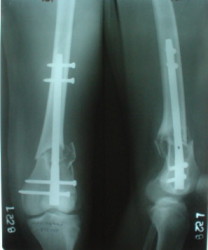

I attached an example of C2 fracture with result of the same technique in 5 months.